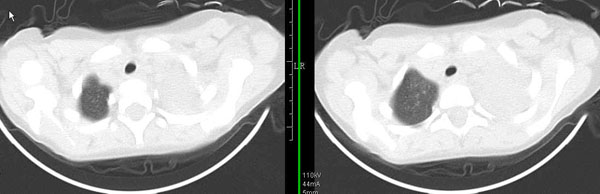

男孩,4岁,发热咳嗽4天。

下面补充ct图片:

此病人是我接手的,发热、咳嗽来做胸透,透视见左侧肺野大部密实,纵隔、心影明显左移,呼吸示纵隔摆动、膈肌矛盾运动(透视下采集了几幅图片),左肺动度明显减弱。询问病人家长,没有吃花生米等呛咳史。由于其影像特征明显,当时诊断:考虑左侧支气管异物并阻塞性肺不张、肺炎。

病人去上级医院支气管镜取出了异物。今天询问上级医院耳鼻喉科主任(是我同学),得知病人异物为胶冻样合并有少许白色粉末,后小儿说晚上喝药片时呛咳过,考虑当时为药片阻塞;另外支气管镜检发现小儿左侧支气管发育略窄,经住院抗炎治疗,现病人基本康复。

多谢各位关注及精彩点评!追踪病人结果时才知道还做过ct检查!对不起!有点晚了,刚刚下载,上传供大家参考!